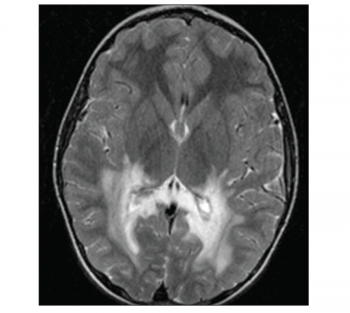

The remainder of the waking record showed no definite epileptiform features. Subsequent magnetic resonance imaging (MRI) of the brain demonstrated extensive diffuse deep white matter high signal change extending inferiorly along the white matter tracts as far as the superior aspect of the pons and brain stem on axial fluid attenuated inversion recovery (FLAIR) and axial T2-weighted sequences.

Extensive high signal changes were seen in the posterior corpus callosum. These extensive changes were bilateral and symmetrical showing moderate peripheral rim enhancement post-gadolinium administration.

Figure 1. Axial T-weighted image showing bilateral extensive white matter lesion in the occipital lobe(click to enlarge)